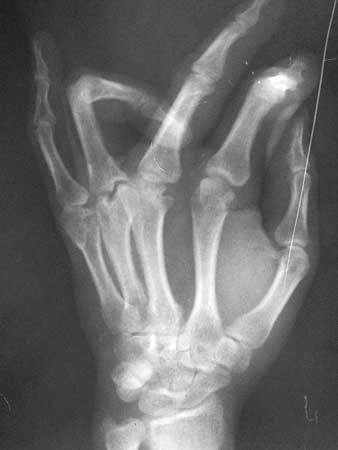

男性患者,31岁,中指和无名指活动障碍,无名指近节指间关节屈曲。

挛缩屈曲畸形,看看有无外伤、烧伤形成的瘢痕,指间、掌指关节为继发性改变。